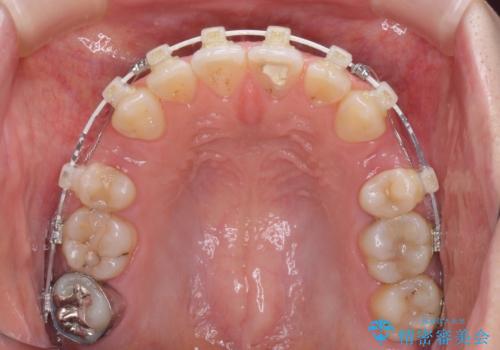

- 矯正装置

- 審美装置

治療は順調に進み、予定された期間で終了することができました。